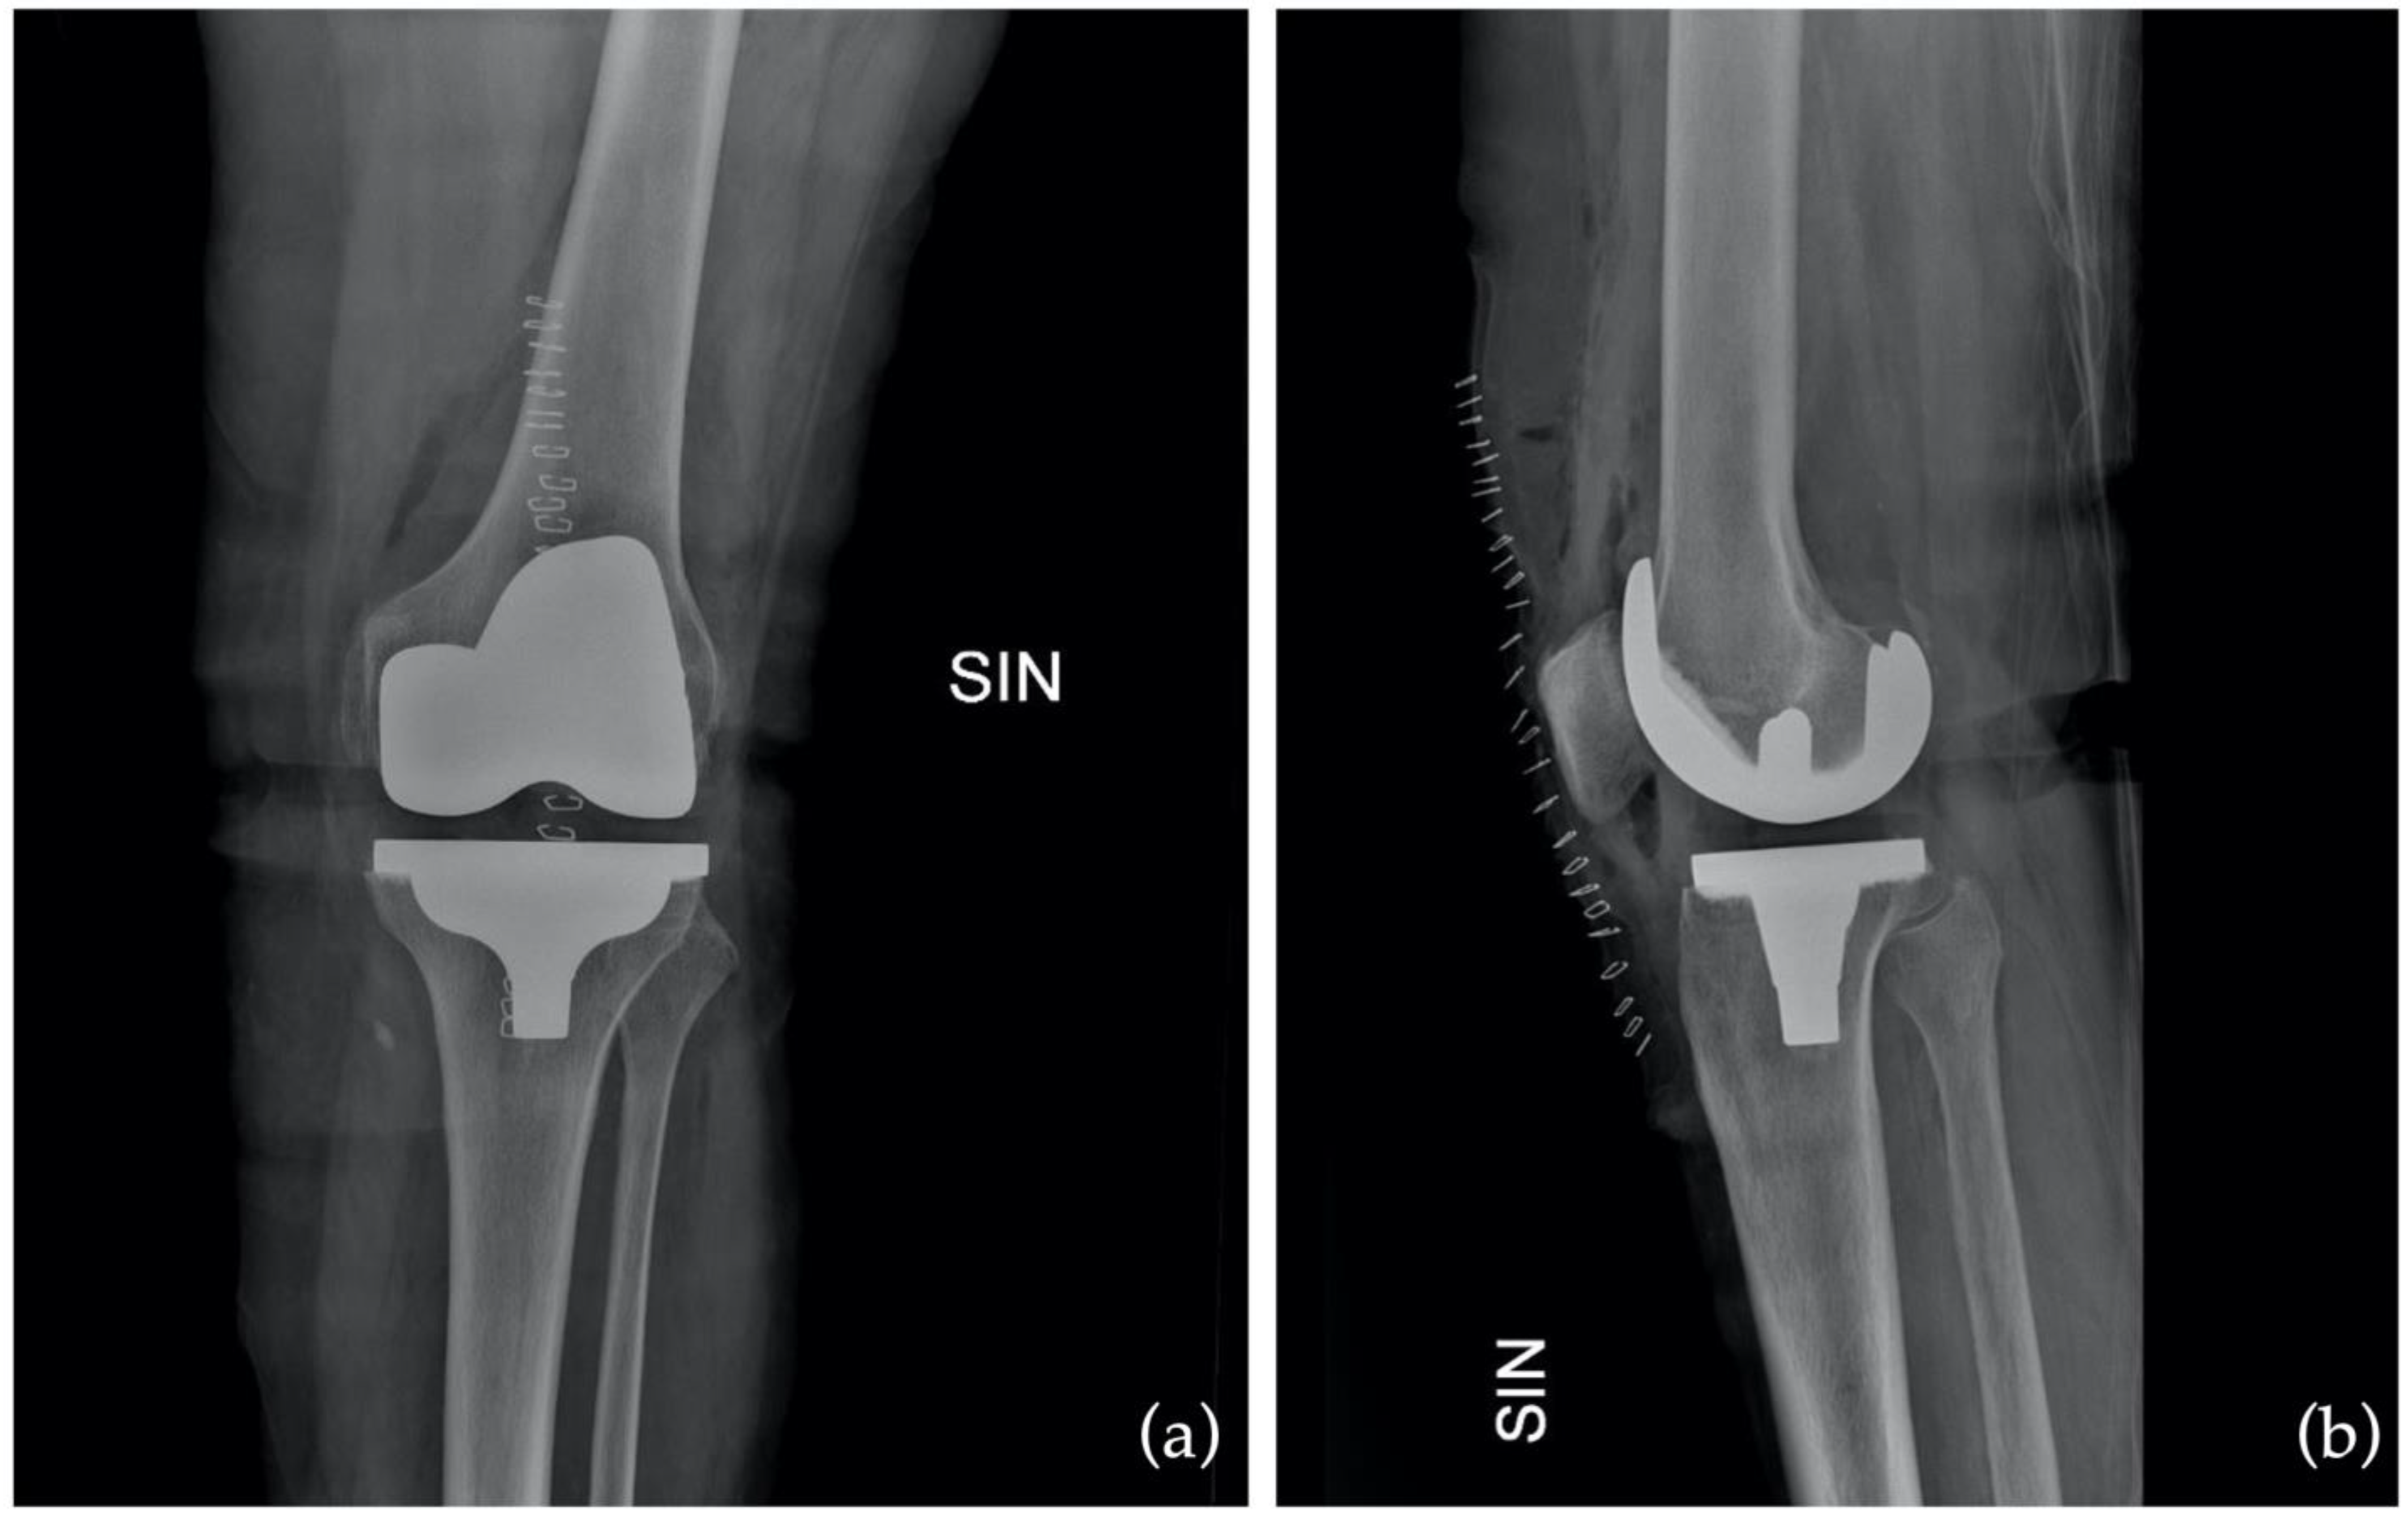

Figure 7.

Postoperative X-ray in anteroposterior (AP) as (a) and in latero-lateral (LL) as (b).